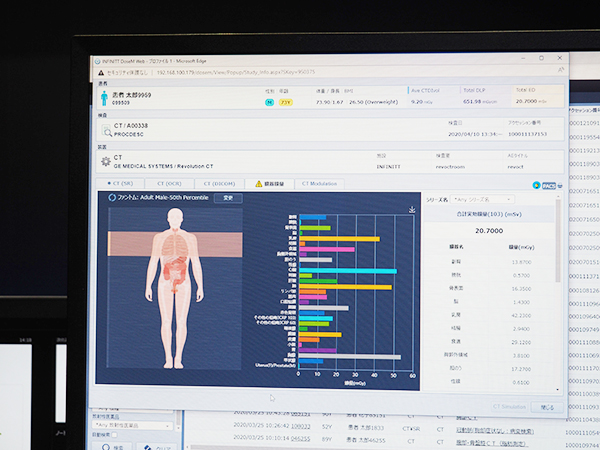

また,PACSの起動とともに未読リストを表示,重要所見の見逃しを防ぐ既読管理機能を搭載するほか,被ばく線量管理システム「INFINITT DoseM」では,実効線量のシミュレーションなどにより,被ばく線量の最適化を支援する。

被ばく線量管理システム「INFINITT DoseM」では,実効線量のシミュレーションなどが行える